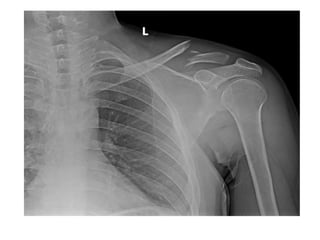

Shoulder Region

• 1st Year- Head of

humerus

• 2nd –Greater tuberosity

• 5th year- Lesser tub.

• 6th Year- Fusion of upper

end of humerus into one

mass

• FUSION

• 20th Year - Fusion of

upper end of humerus

with shaft